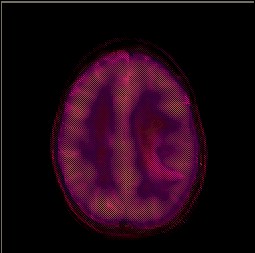

Figura 5. (a) Imagen R1G1B1. (b) Canal R1 (c) Canales R1B1. (d) Canales R1G1.